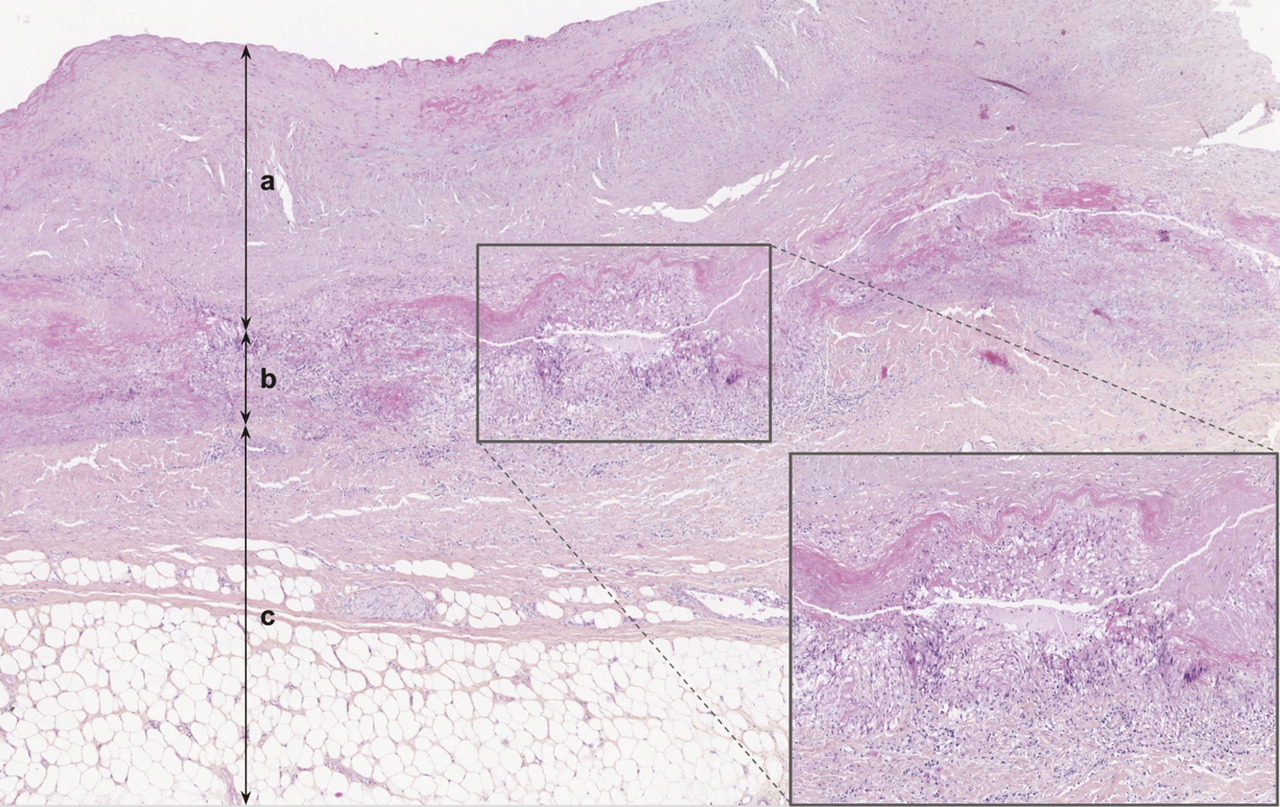

L’anatomopathologie retrouve un infiltrat inflammatoire granulomateux

Sur le plan anatomopathologique, lorsqu’une pièce opératoire est disponible, on observe, dans la forme active, une panartérite des artères de gros calibre, segmentaire et focale, caractérisée par un infiltrat inflammatoire granulomateux (ou gigantocellulaire) qui dissocie la paroi vasculaire (fig. 1 ). Cet infiltrat granulomateux est constitué par des macrophages, des cellules épithélioïdes et des cellules géantes. Des granulomes compacts peuvent être observés. S’y associe une composante lymphocytaire ou lymphoplasmocytaire. À l’inverse de l’artérite à cellules géantes (ou maladie de Horton), l’artérite de Takayasu est souvent à prédominance médio-adventicielle (avec atteinte de la partie externe de la média et de l’adventice). La limitante élastique interne est le plus souvent préservée tandis que la limitante élastique externe peut disparaître, avec fréquemment des lésions d’élastophagie et/ou d’élastolyse. L’intima est le siège d’une hyperplasie secondaire à la prolifération de myofibroblastes, pouvant réduire le calibre de la lumière artérielle. Les thromboses sont exceptionnelles.

À terme, ces lésions inflammatoires peuvent laisser place à une fibrose cicatricielle diffuse pure, caractérisée par un anneau fibreux médio-adventiciel, qui peut aider au diagnostic.14